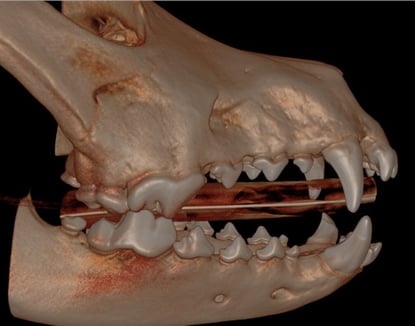

Henry, a 4-year-old neutered male Labrador Retriever, was referred for evaluation due to a broken lower left canine tooth (304), suspected to have occurred several months prior as a result of an accident.

Below: 3D Overview before procedure: (left and right)

A root canal procedure was performed on the lower left canine tooth 304, which presented with a complicated crown fracture. To access the pulp chamber, we employed a Piezo opener, ensuring precise and efficient entry.